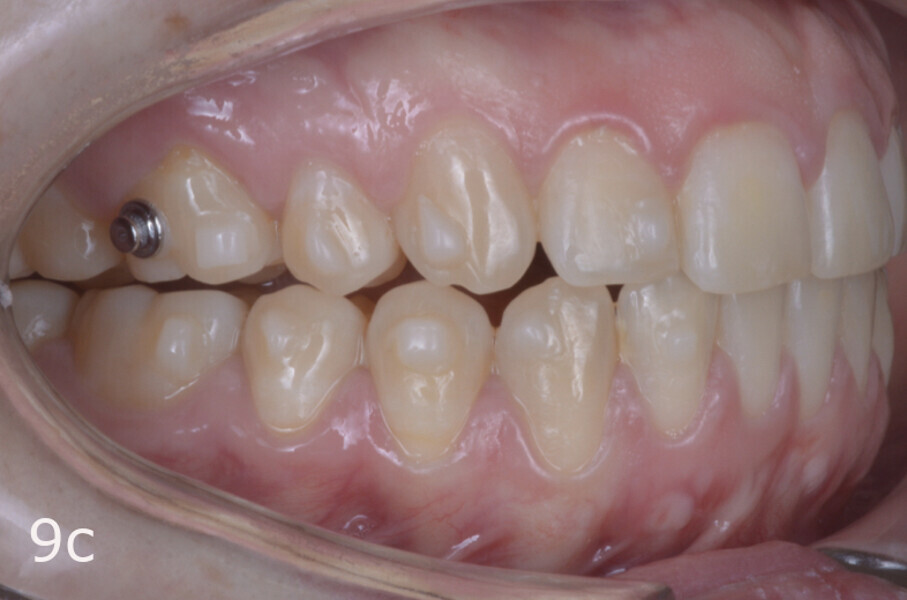

The treatment objectives included closing the anterior open bite, achieving a bilateral Angle Class I relationship and a proper overjet and overbite, correcting the midline discrepancies, and achieving a profile harmonisation. The treatment plan consisted of orthodontic camouflage treatment with asymmetric distalisation in three of the four quadrants using Invisalign aligners (Align Technology) and third molar extraction. The Invisalign Comprehensive package was chosen, and 63 pairs of aligners were used (Figs. 7–10). Each aligner was worn for 20 hours a day for one week each. The use of Class III elastics on both sides was indicated. Afterwards, ten refinement aligners were needed to improve the interdigitation on the right side (Figs. 11 & 12).